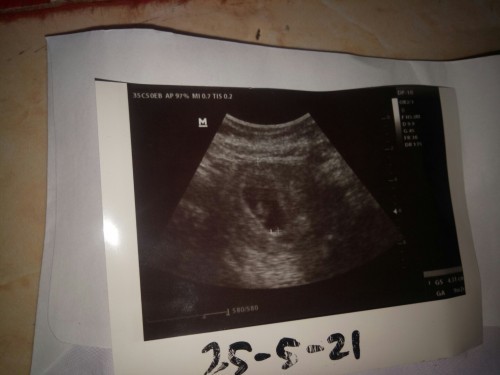

Bun maaf mau nanya kan saya terakhir haid tgl 17maret-21 maret lalu tgl 25 mei saya USG itu usia kandungan masih 9minggu 2hr, lalu kira-kira usia kandungan saya skrg brp minggu ya soalnya kalau liat di aplikasi udah 15minggu 1hari, tapi kalau ikutin USG baru 14minggu tigahari??? mohon bantu dijawab ya bun soalnya baru hamil anak pertama jadi blm paham, terimakasih bunda" 😊 #bantusharing #seriusnanya